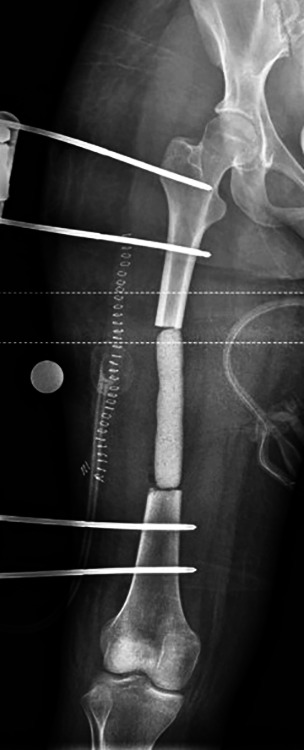

Aim: The treatment of massive diaphyseal tibial bone defects remains challenging with poor results seen from treatment modalities other than bone transport (BT). Current methods of BT require lengthy periods in a circular external fixator. Despite recent modifications in BT techniques via circular external fixator such as multifocal transport and immediate intramedullary nailing after docking, circular external fixation remains poorly tolerated with a high complication profile. Newer technologies such as magnetic lengthening nails have shown promise to provide alternatives to BT without resorting to long-term circular external fixation. Plate-assisted bone segment transport (PABST) has demonstrated success as an all-internal BT technique. Prior case reports have shown a modest ability to treat massive defects with varying success.

Technique: A novel all-internal cable and pulley augmentation to a PABST technique for a massive (185 mm) tibial defect was utilised during a retrograde transport. The authors describe a patient scenario in which this augment allowed continued transport that could not be treated with an additional Precice nail recharge.

Conclusion: Augmentation of PABST with a cable and pulley construct can successfully treat massive diaphyseal defects.

Clinical significance: This cable and pulley modification to PABST allows for the treatment of massive tibial defects without the need for magnetic lengthening nail exchange or conversion to external fixation.